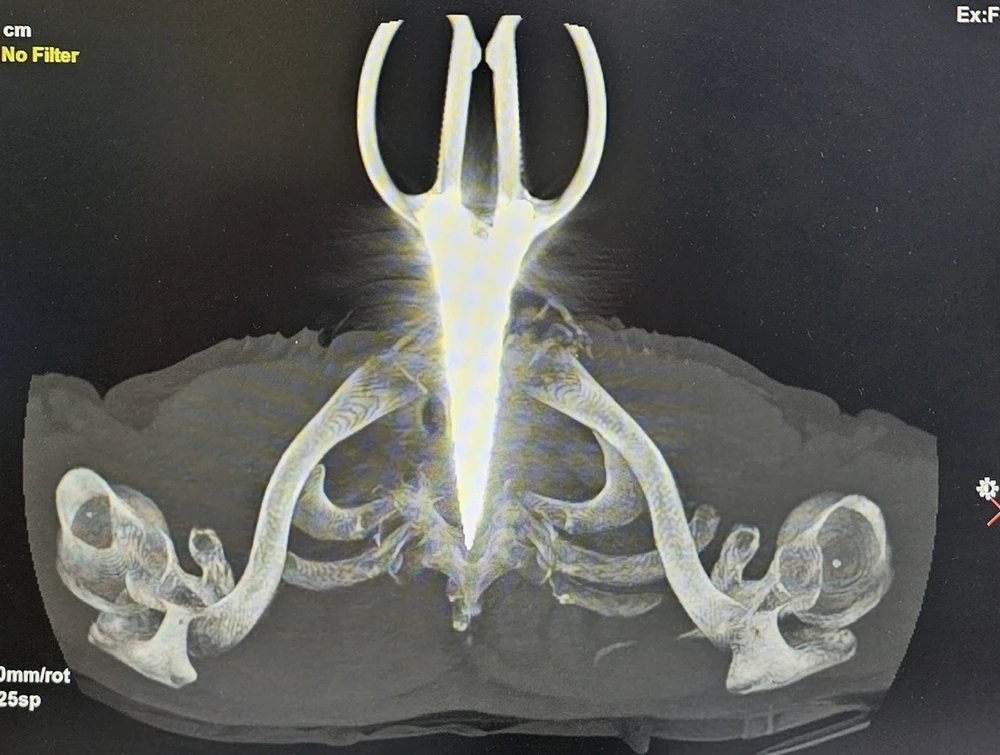

kéo đâm xuyên cổ người đàn ông

Phim chụp chiếc kéo đâm xuyên cổ bệnh nhân. Ảnh: BVCC